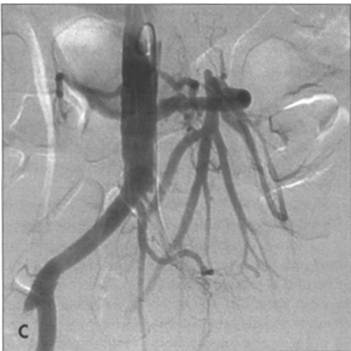

FIG. A - Schematic representation of revascularization of the SMA with: bypass taking care to avoid kinking and obs-

truction B - Or re-implantation of SMA into the aorta. C - Angiographic appearance of aorto-SMA bypass with vein graft.

There is co-existing left common iliac occlusion. D - Angiographic appearance of re-implanted SMA into aorta, which has